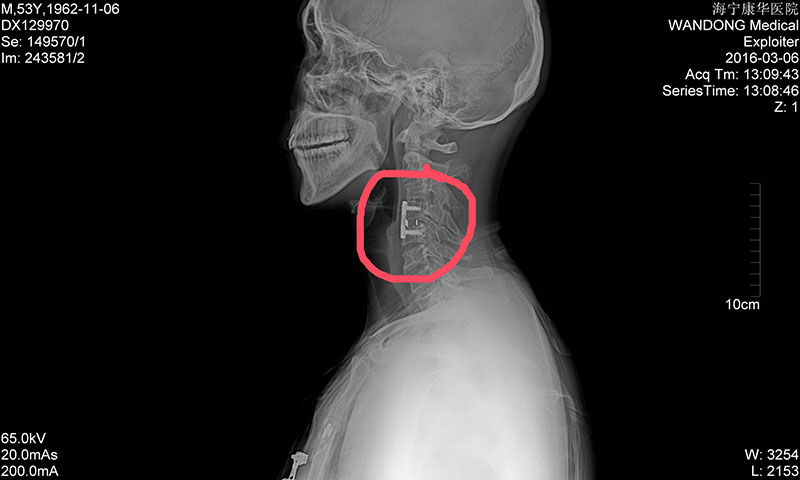

经初步诊断,老田脊髓损伤(颈段):颈椎脱位、左侧颈4椎体骨折、颈4椎板骨折、颈4棘突——高位截瘫!如霹雳般的消息传至家人耳中,妻子惊惶无措、泪流不止:才50多的人,就这样瘫了,以后家该怎么办?

8月18日,老田被第一次推进手术室进行颅骨牵引术,家人揪着心等完了全程,终于等到老田顺利出来。8月31日,老田再一次被推向手术台,妻子一直紧攥着手里的包不曾松开。门外的人坐立不安,门内——颈椎前路切开复位、钢板内固定术、颈4/5椎间融合器植骨融合术、左胫骨取骨术,一项项复杂的工作在蒋林海与张凤军的手下进行着……“成功了,没事了。”当蒋林海微笑着走出手术室,凤娟忍不住掩面而泣,连感激都梗在喉间,一个字都说不出来。